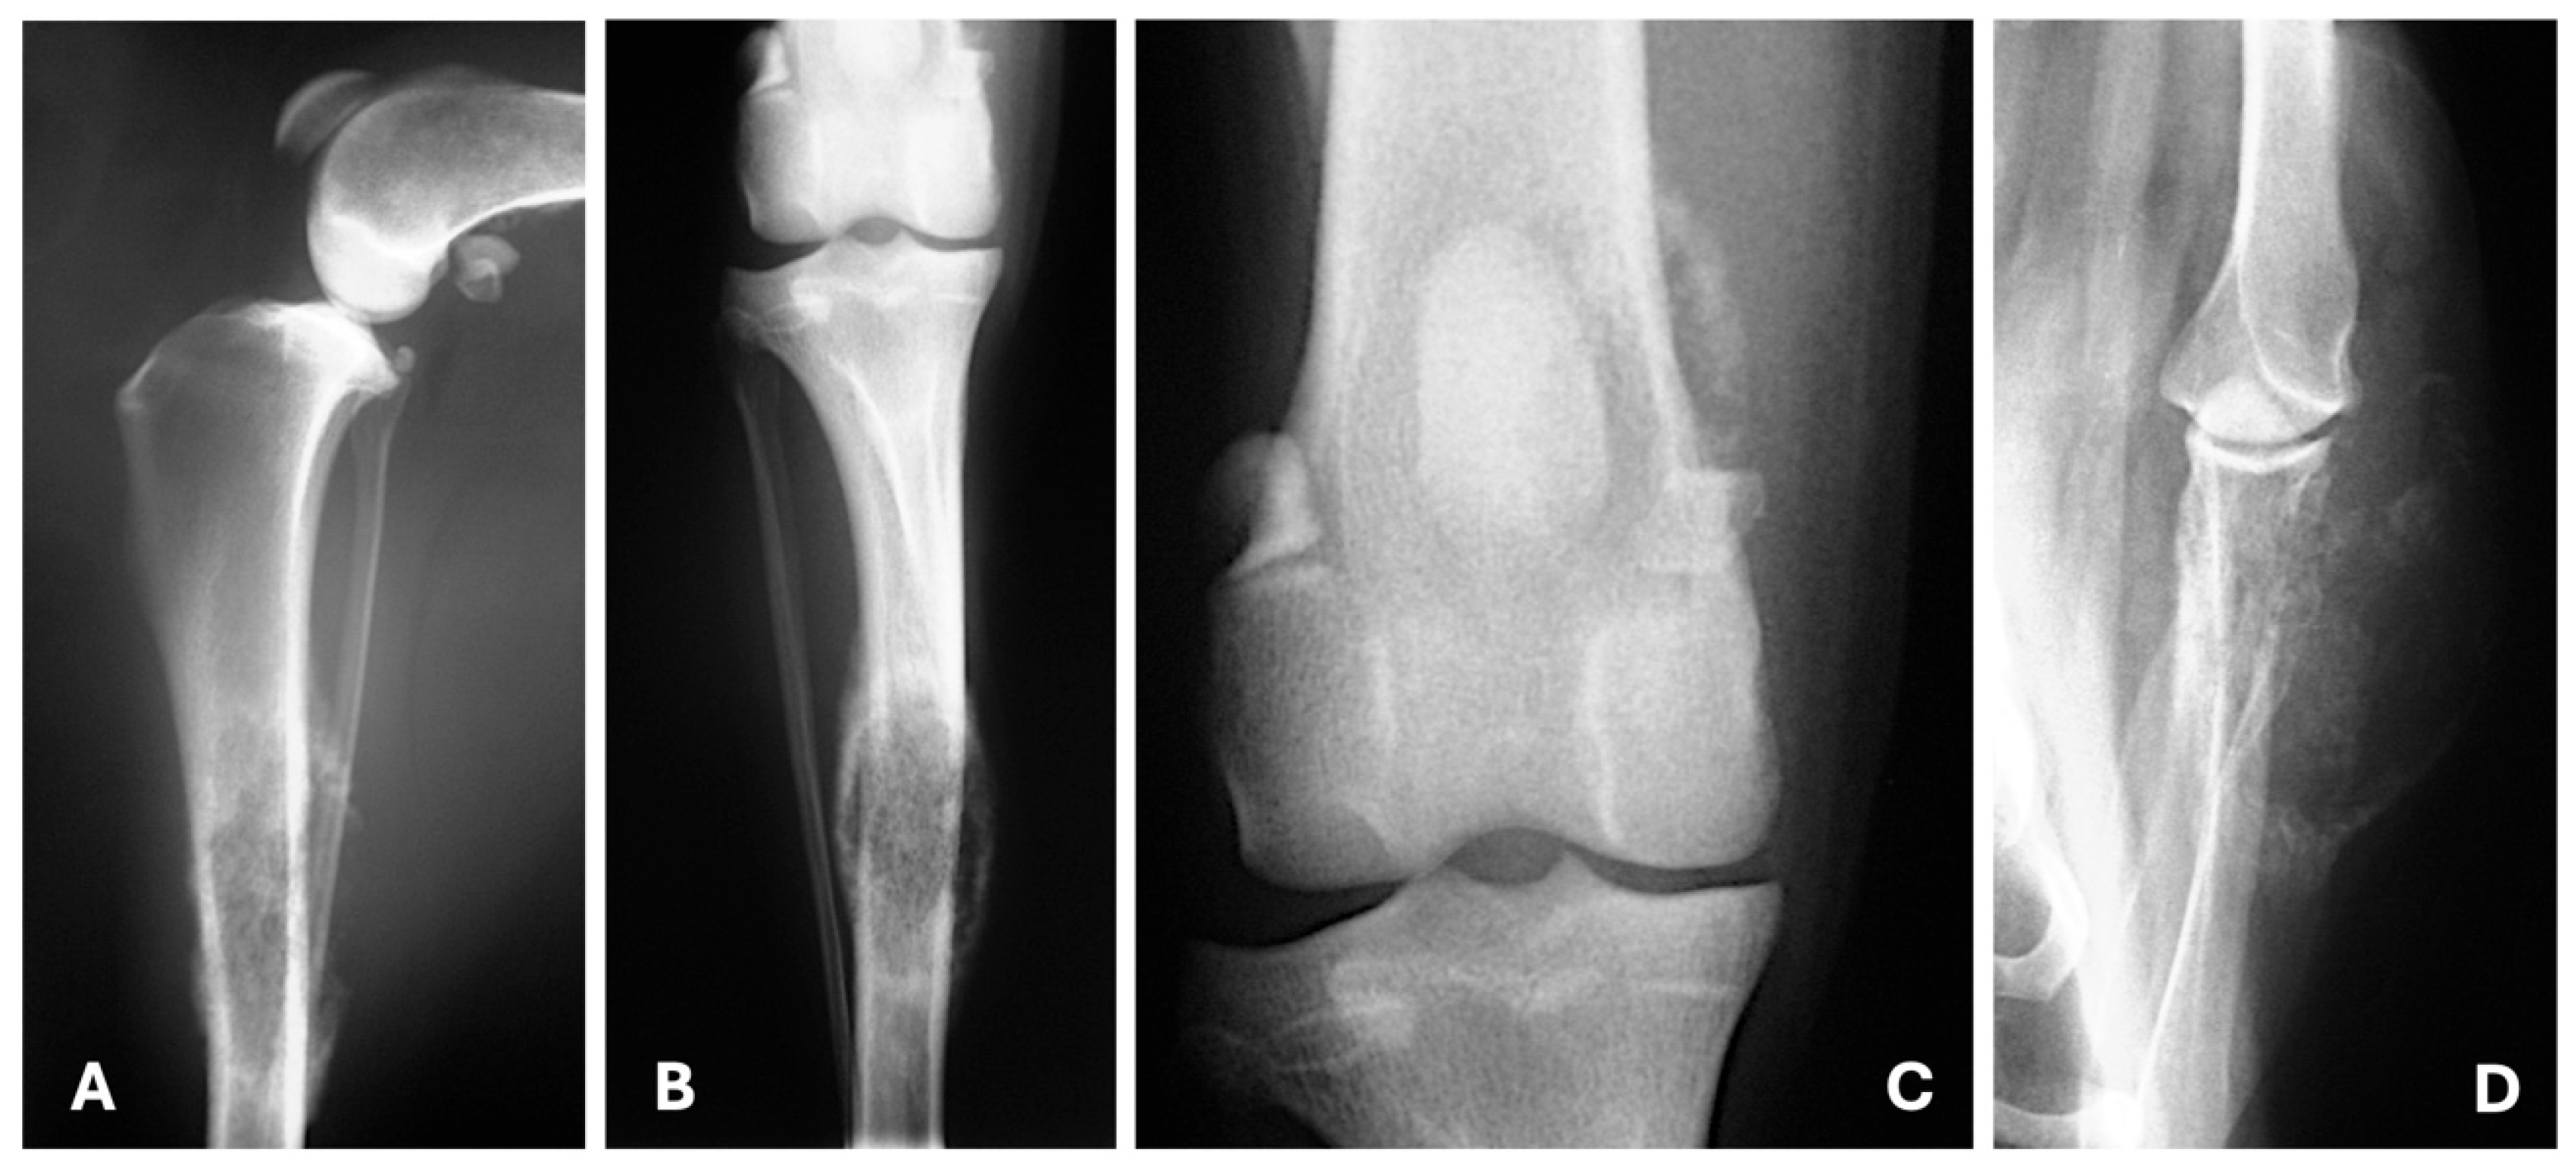

- Baptista, C.S.; Santos, A.A.; Villagrasa, M.H.; Matos, A.J. Diagnostic Imaging Findings of Uncommon Sites for Distant Metastasis in Canine Mammary Tumours—Abstracts from the annual meeting of the european college of veterinary diagnostic imaging and european association of veterinary diagnostic imaging. Vet. Radiol. Ultrasound. 2014, 55, 651–679. [Google Scholar] [CrossRef]

- Kim, S.; Kwon, K.; Choi, H.; Lee, Y. Evaluation of Mammary Gland Calcification in Dogs: Radiography and Computed Tomography. J. Anim. Reprod. Biotechnol. 2017, 32, 183–192. [Google Scholar] [CrossRef]